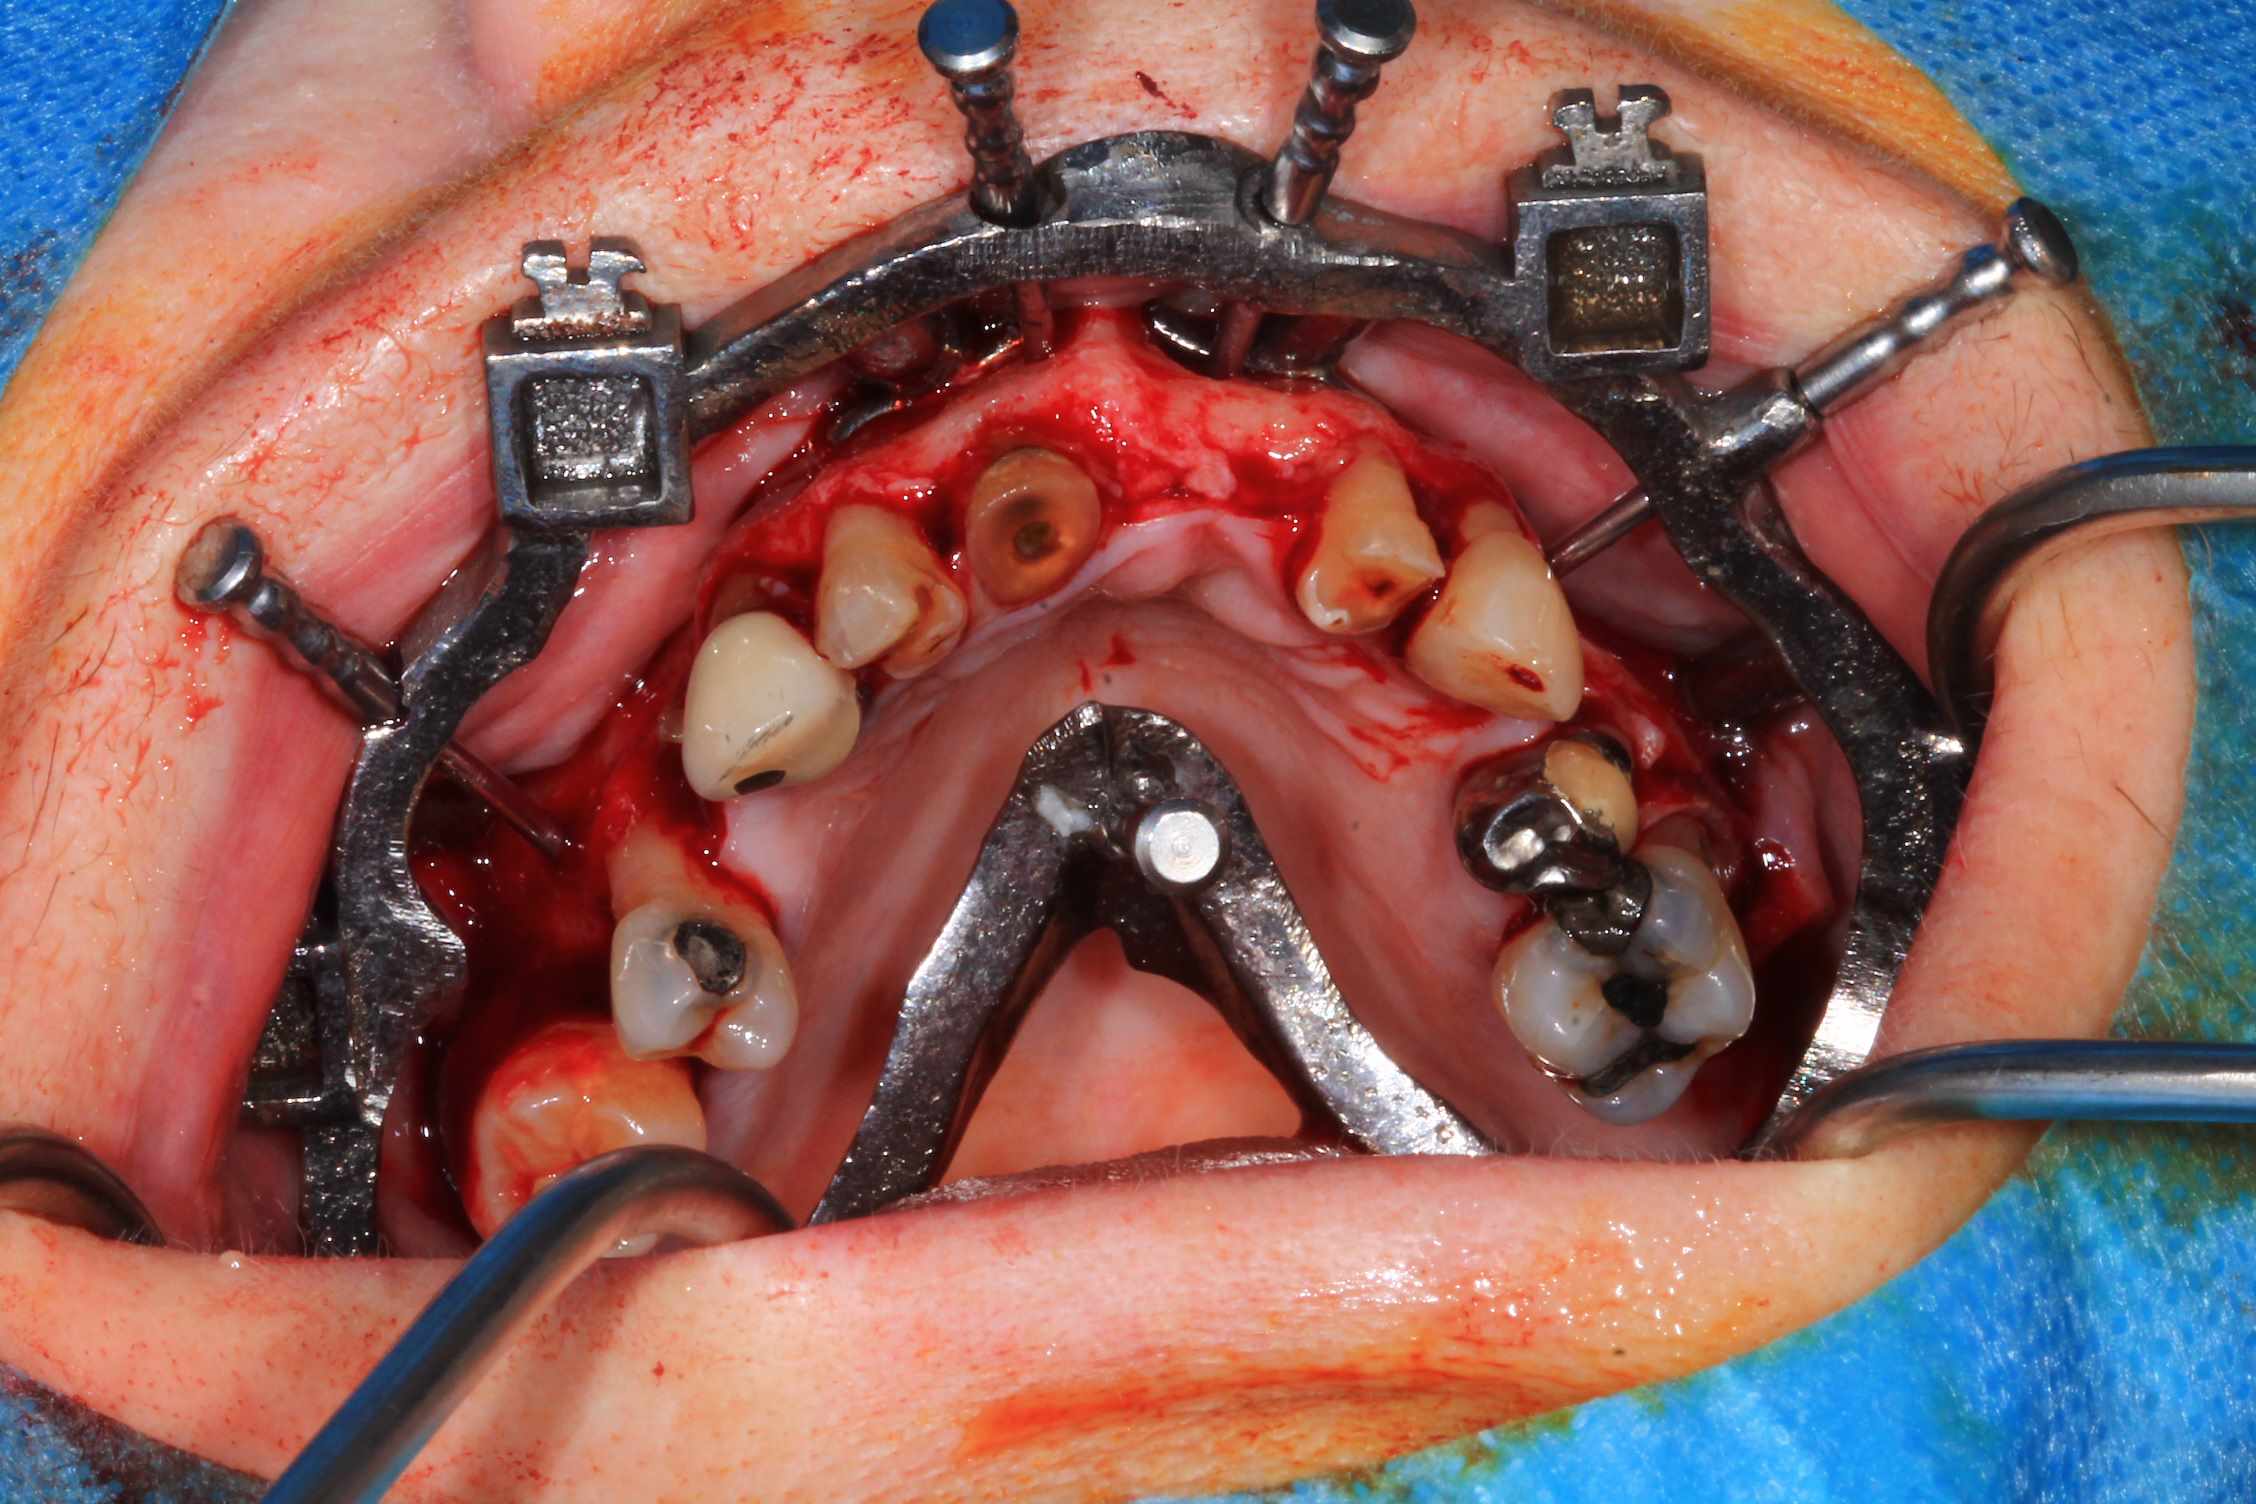

Cas 5 : extraction et all on 4. en bas , pas du tout d'os : décision de bridge complet avec une extension de chaque coté.

Modélisation : labo lio. Design et impression du guide : Teeth projet. Bridge full zircone katana myio rosenscrew en mise en charge instantanée , labo LIO.

Guide a etage avec fixtion de l'etage clavette par rapport aux dents avant extraction. Extraction.

Fixation du guide de forage sur le guide clavette. pose des implants, des piliers ( tres classique ), et du bridge zircone rosenscrew. Stickybone The Graft, sutures suspendues et résultat post op et un mois.